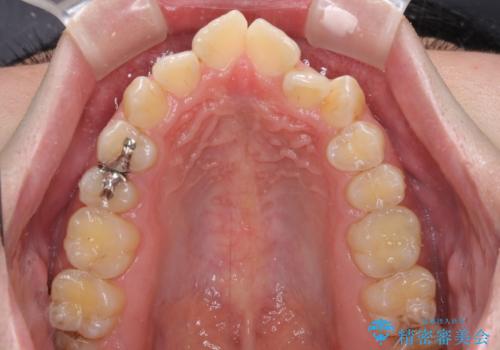

- 上下前歯のデコボコを気にして来院された患者様です。

ワイヤー矯正でもマウスピース矯正でも可能でしたが、短期間で、自身の手を煩わせることなく治療を行いたいとのことで、ワイヤー装置にて矯正治療を行うこととしました。

当初予定通り、1年間で治療を終えることができました。